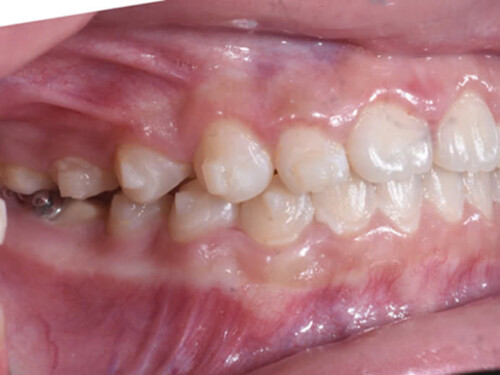

Hình 2: Tổn thương đốm trắng xuất hiện trên mặt ngoài răng 13 và phía gần răng 12